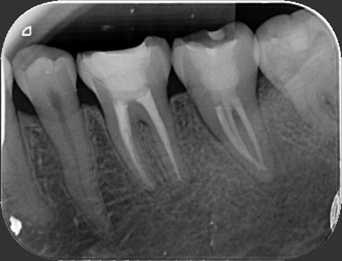

經 X 光與 CBCT 斷層影像評估後,牙髓病專科(根管專科)顏意欣醫師發現,這是一顆鈣化合併嚴重彎曲的根管。

這類狀況非常棘手——鈣化會封住根管開口、彎曲角度又大,若用傳統器械治療,極易發生器械斷裂或清潔不全。